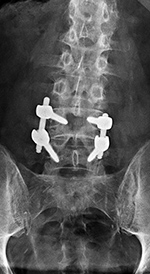

| Harms vertebral cage (AP view) |

From Hunter, 2004 |

| Vertebral corpectomy with vertebral cage and left lateral side plate |